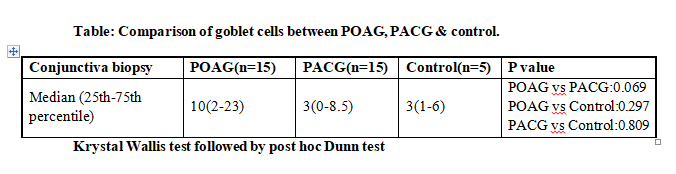

Cellular profile in PACG with median goblet cells at 3 was non significantly less than POAG at 10 & equal to control at 3.

Comparison of POAG group with control was NS, however that of PACG with control did show statistically significant difference (p=0.002). POAG vs PACG was not statistically significant. Number of goblet cells were 3 (control), 10

(POAG) & 3 (PACG). Comparison of both POAG & PACG with controls was NS. POAG vs PACG was NS.